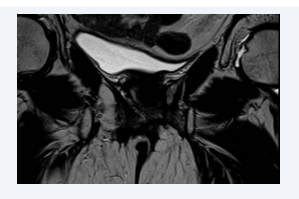

In July 2017, the patient experienced another recurrence in the left vulvar region with involvement of the elevator any muscle. An MRI on July 9, 2018, revealed a 33 mm solid mass infiltrating surrounding tissues and partially ulcerating, with apparent invasion of the anterior aspect of the left elevator any muscle (Figure 1)..

Figure 1: Giugno 2007.